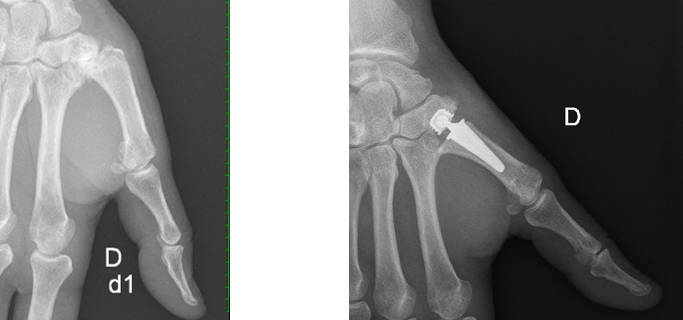

Rhizarthrose

La rhizarthrose est l'arthrose de l'articulation trapézo-métacarpienne à la base du pouce.

Une radiographie de la base de pouce est nécessaire au diagnostic

Prothèse trapézométacarpienne

Prothèse totale de pouce